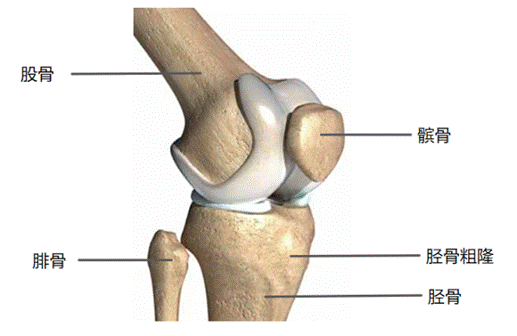

膝关节构成骨:股骨下端、胫骨上端和髌骨。

图. 构成膝关节的主要骨骼